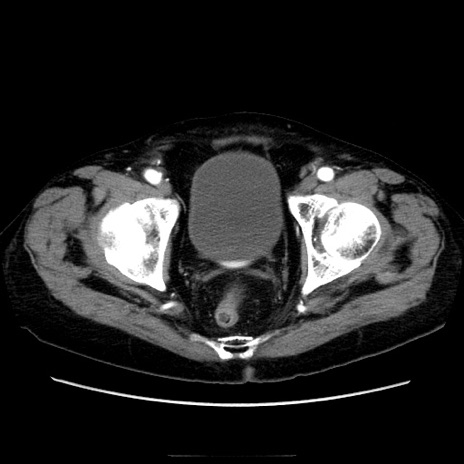

冠状断像

症例21(横断像)

【症例】70歳代男性

【主訴】腹痛

【現病歴】肝硬変・肝細胞癌にてかかりつけの方。約9時間前に食後より腹痛出現。症状が徐々に増悪し、嘔吐出現したため来院。

【既往歴】肝硬変、肝細胞癌(RFA、TACE後)

【身体所見】意識清明、表情苦悶様、BT 36℃、BP 129/78mmHg、P 88bpm、SpO2 97%(RA)、右上腹部から心窩部にかけて圧痛あり、反跳痛なし、筋性防御あり。

【データ】WBC 5800、CRP 0.16